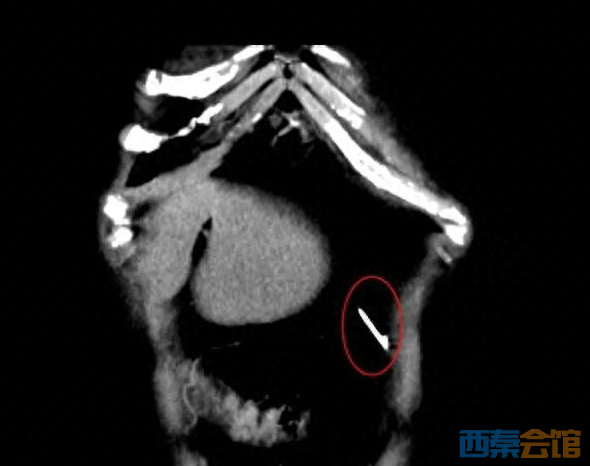

越想越觉得危险,莫女士赶紧到附近的医院做了拍片检查,果然在腹腔内发现一枚针样金属影。但医生告诉她,由于异物太小,手术不一定能找到,且存在风险,建议到上级医院就诊。

CT检查显示,莫女士体内确实有一根针。

于是,莫女士来到广西医科大学附属肿瘤医院胃肠外科寻求帮助。经腹部CT检查,发现她腹腔内确有一枚针状物。科室专家团队制定了手术方案,为莫女士进行腹腔镜下腹腔异物取出术。